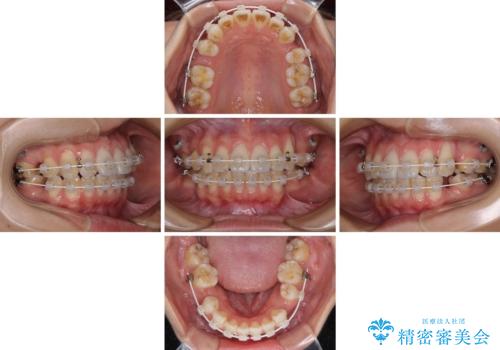

- 八重歯と口元の突出感を気にして来院された患者様です。

歯列が前方に突出しており、上下の正中がズレていたため、左側は上下第一小臼歯を、右側は上下第二小臼歯を抜去し、ワイヤー装置による矯正治療を行うこととしました。

当初はインビザラインによる矯正治療をご希望でしたが、正中を合わせたいことや、口元の突出感を改善したいことから、ワイヤー矯正を強く推奨しました。

治療期間は2年に満たず、スッキリとした口元に仕上がりました。